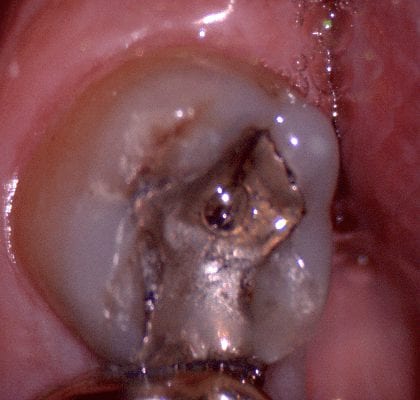

Upon preparing the second molar for full cuspal coverage, the lack of clearance necessitated a refining the preparation. The great part of digital dentistry is that you don’t have to take a whole new impression.

You can just selectively crop out the area that needs refinement, protect the areas you are satisfied with, and fill in the areas that are missing data. You can see how this case was managed in this video and how the final buccal bite was captured. We always recommend that you capture the bite at the last step so that you can verify clearance through the camera itself.